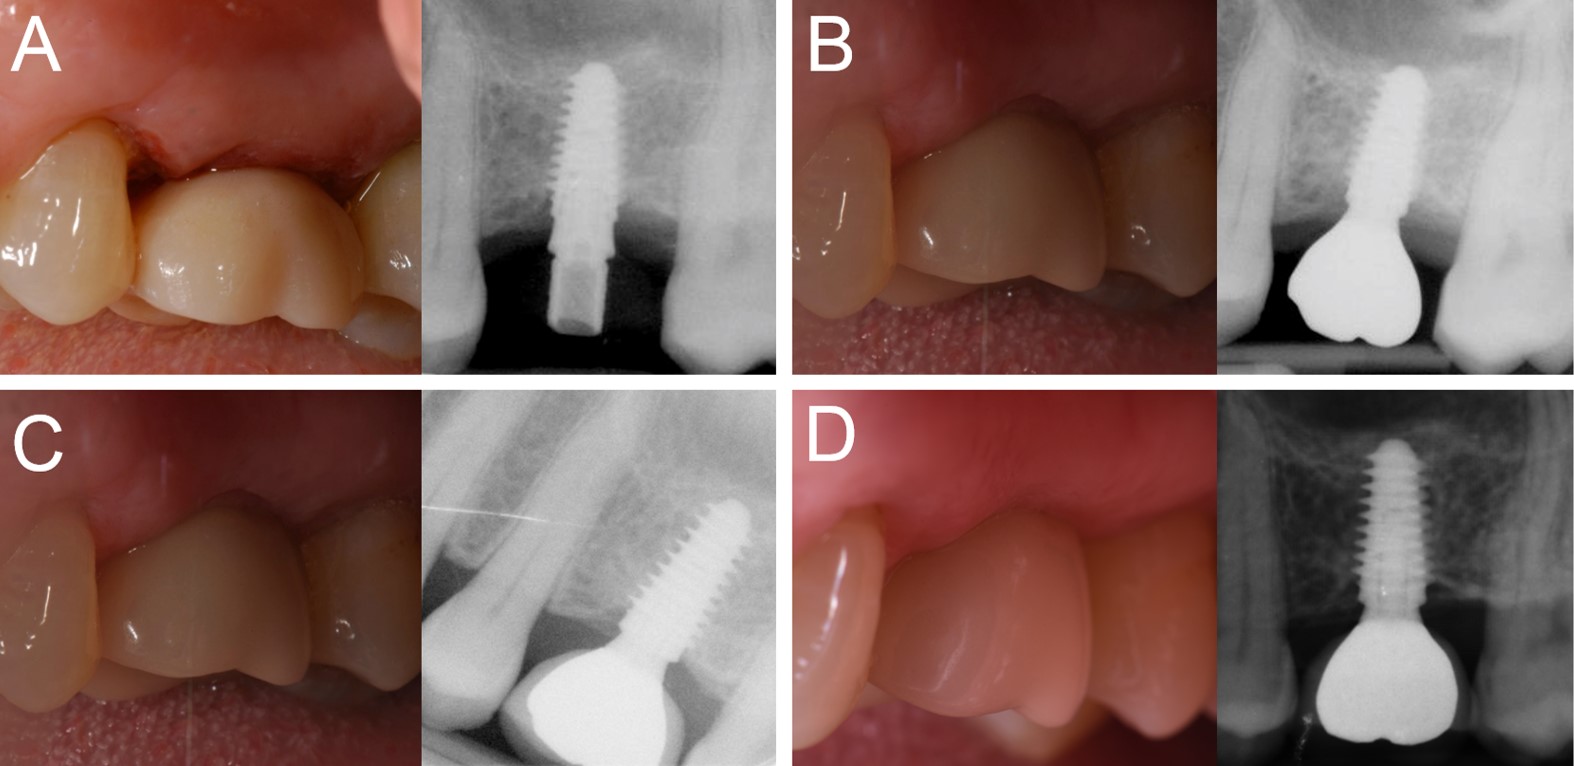

Overall, five patients could not attend the 4-year control visit and were therefore classified as drop-outs, despite the fact that the implants were still in operation. However, 4 years after insertion, only one implant was lost, in the posterior maxilla (second premolar, healed site) of a smoking woman, 48 years old at the time of surgery. The failed implant was 3.5 mm in diameter and 10.0 mm in length and was installed in bone type III. This implant failed during the first healing period, exactly two months after the insertion and immediate functional loading, as it lost stability, in the absence of infection. All the other implants were stable; therefore, the overall 4-year implant survival rate was 97.6% (patient-based, with 40/41 fixture in the survival category) and 98.1% (implant-based, with 51/52 implants in the survival category), respectively (Figures 1-4).

Figure 4.Immediate loading of a first maxillary molar (#26) placed in a healed ridge: (A) The implant is placed and loaded within 48 hours of the surgery; (B) three months later, the final metal‒ceramic crown is delivered; (C) the 1-year clinical and radiographic control; (D) the 4-year clinical and radiographic control.